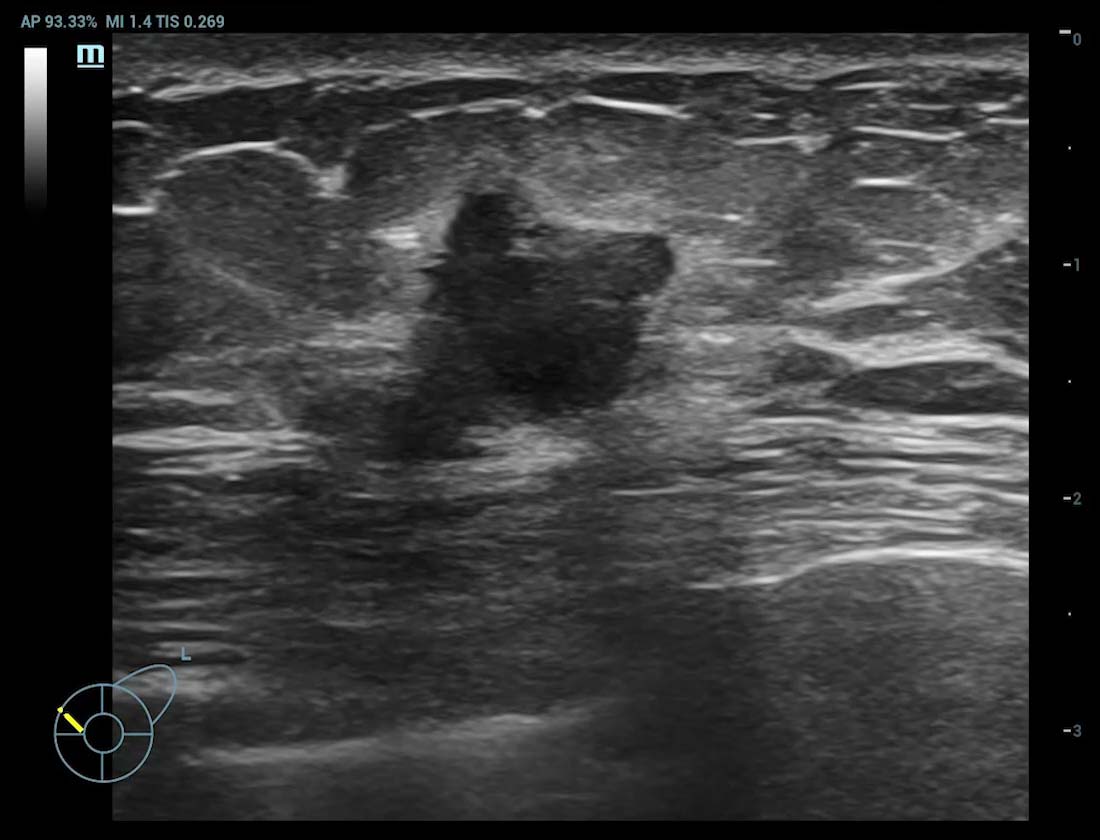

Borstkanker is wereldwijd de meest gediagnosticeerde vorm van maligniteit. Het is de meest voorkomende doodsoorzaak door kanker bij vrouwen. Vroegtijdige opsporing van borstkanker is essentieel omdat pati?nten in een vroeg stadium een betere prognose hebben. Als antwoord hierop biedt de Resona R9 Platinum Edition een oplossing voor multi-parametrische borstechografie die vroege detectie van borstkanker, nauwkeurige diagnose en behandeling van borstkanker en baanbrekend klinisch onderzoek mogelijk maakt.

HD Scope

Verbeter de detailinformatie en het beeldcontrast op specifieke gebieden, vooral nuttig voor de weergave van de randen en de binnenstructuur

HD Scope

Smart Breast kwaadaardig

Smart Breast

Smart Breast is een analyse- en rapportagetool voor borstechografie om de klinische routine van borstechografie nauwkeuriger en productiever te maken. Het systematische beheer van meerdere laesies en de beoordeling van vier vlakken garandeert meer diagnostische informatie. Ondertussen verbetert de gestroomlijnde geautomatiseerde workflow de effici?ntie bij het scannen van borsten.

Borstmassa cUMA

Borstmassa